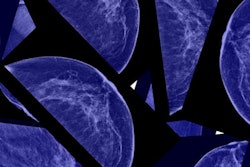

We also have the first two videos from ECR 2018: an exclusive interview with ECR 2018 President Prof. Bernd Hamm about Brexit, artificial intelligence, and attendance numbers and also an interview with Dr. Elisabetta Giannotti on breast imaging and the future of mammography. You won't want to miss them.